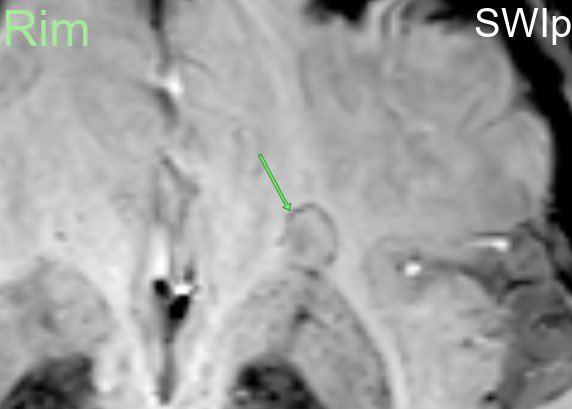

🚨🧠 Big news for #MultipleSclerosis diagnosis! 🚨 At #ECTRIMS2024, the 2024 McDonald Criteria were just released by Xavier Montalban and this changes everything for #Neuroradiology and #MSDiagnosis. Here’s what you need to know 🧵👇